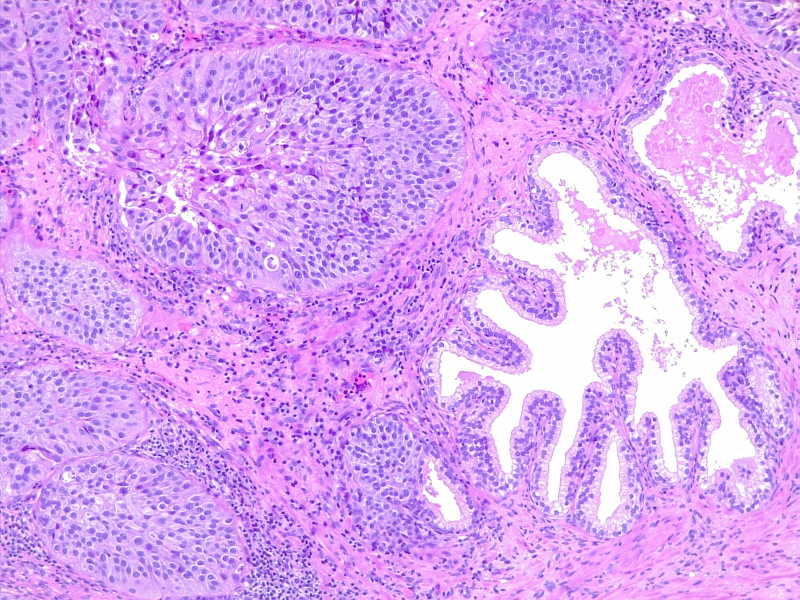

图4: 尿路上皮癌,神经周围浸润。10x H/E。医学博士 Fabiola Farci 供稿